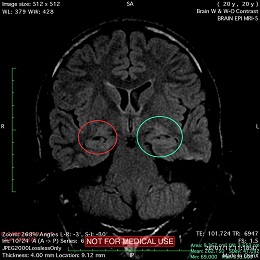

A subtle linear band intensity extending between deep posterosuperior aspect of right Sylvian fissure and posterior aspect of corpus of right lateral ventricle (isointense with gray matter on all sequences). These MRI findings strongly suggest "Type II (Taylor type) focal cortical dysplasia (transmantle cortical dysplasia)" or "transmantle gray matter heterotopia". Virtually, they may be representing two different names for the same entity.

Secondary hippocampal sclerosis is identified, bilaterally (secondary to long-term intractable epilepsy).